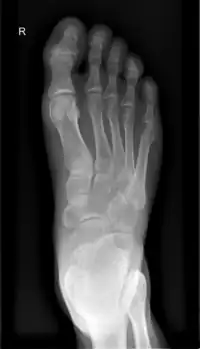

足,又称腳、跤,解剖学上指陸地脊椎動物腿的末端、支撑该生物的部分。大多数双足及许多四足动物的脚有以下结构:踝关节,脚跟,足弓,脚趾。脚是人和某些脊椎动物肢体的末端接触地面的部分,是人体的负重器官和运动器官。在许多有脚的生物中,脚是腿末端的独立器官,由一个或多个部分或骨骼组成,通常包含爪子和趾甲。

在解剖学上,足部的定义位置是位于踝部远侧,分为足背、足底和足趾。而足底(跖)涵盖了跖丘(ball of the foot,足趾和足弓之间)、足弓、足跟;足趾再细分趾根、趾身、趾端、趾甲等部位[1]。但在口语中,人类的“脚”可能较广义,可包含足踝,甚至腿部。

脚的构造分三个部分,即前、中、后脚部。这三个分布的构造及功能都不一样。[2]

| 双足骨骼 | 共52块(全身骨骼的六分之一) | 组成足部结构 、关节的钙质等物质的代谢等调节 |

| 双足关节 | 共66个 | 局部各种活动 , 富有弹性等功能 |

| 双足韧带 | 共214条 | 使各关节易于联络活动 , 协调及缓冲压力 |

| 双足肌肉 | 共38条(全身肌肉的43%) | 舒张及收缩之运动功能 , 具有冲击力 |

| 足弓 | 纵弓高度:男性4.74厘米,女性3.13厘米 | 富有弹性 , 缓冲重力 , 减轻震荡 , 保护关节 |